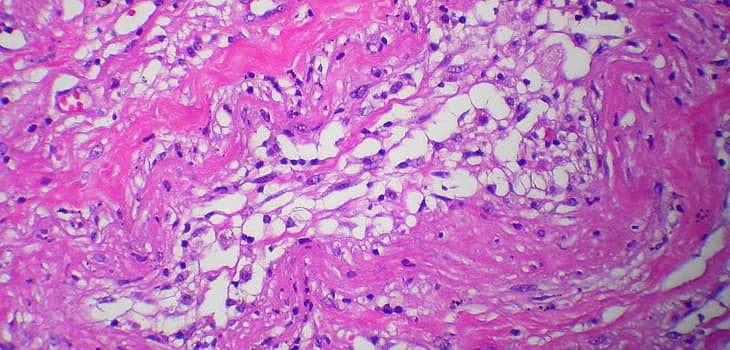

L'utilizzo di MFAT (Micro-Fragmented Adipose Tissue) di Lipogems come terapia infiltrativa negli sportivi è diventato, negli ultimi anni, un trattamento sempre...